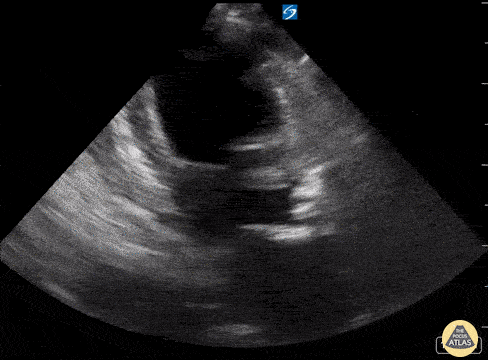

Pictured is an apical 2 chamber view from a 60-year-old female who presented to our ED with acute hypoxic respiratory failure. Note the presence of LVH and LV systolic dysfunction. PLAX view additionally confirmed the presence of critical aortic stenosis; lung views were notable for >3 B-lines per frame; all consistent with her clinical picture of acute cariogenic pulmonary edema. Guillermo A. Obregon MS-4. Central Michigan University Emergency Medicine Residency Additional contributors: Brian Brazeau MD, Harrison Zeitler MD, Therese Mead DO, RDMS, FACEP